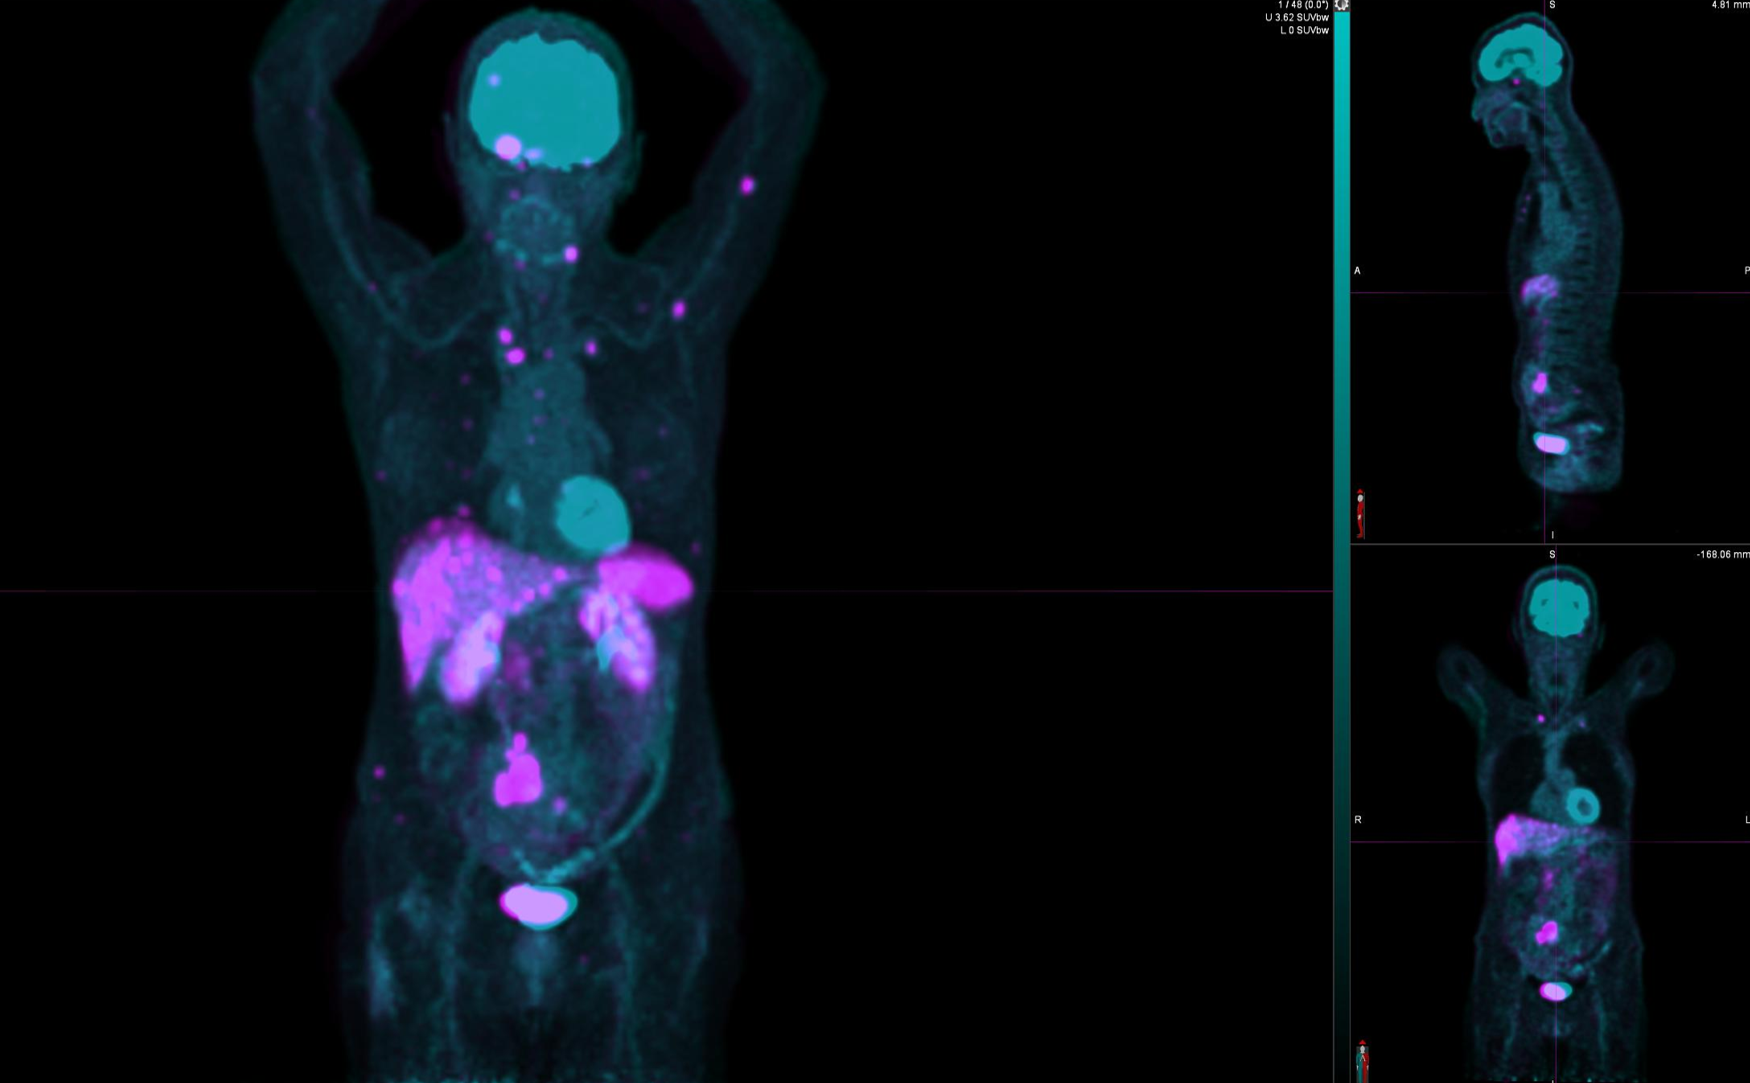

Το Lu-177 PSMA αποτελεί μια στοχευμένη ραδιονουκλιδική θεραπεία για ασθενείς με ορμονοάντοχο μεταστατικό καρκίνο του προστάτη (mCRPC), αξιοποιώντας τη υπερέκφραση του PSMA (Prostate-Specific Membrane Antigen) στα καρκινικά κύτταρα. Προηγείται PSMA PET/CT για ακριβή χαρτογράφηση της νόσου και επιβεβαίωση επαρκούς πρόσληψης του ραδιοφάρμακου. Το Lu-177 PSMA συνδέεται στους PSMA-υποδοχείς, επιτρέποντας στοχευμένη ακτινική δράση υψηλής κυτταροτοξικότητας σε μεταστατικές εστίες οστών και μαλακών μορίων. Η χρήση εξειδικευμένων δοσιμετρικών εργαλείων επιτρέπει την ποσοτική αποτίμηση της δόσης σε κρίσιμα όργανα (π.χ. σιελογόνοι αδένες, νεφροί, μυελός) και στον όγκο, συμβάλλοντας σε εξατομικευμένη θεραπευτική προσέγγιση. Μετά από κάθε κύκλο πραγματοποιείται PSMA PET/CT ή FDG PET/CT (όπου ενδείκνυται), καθώς και στενός αιματολογικός έλεγχος για αξιολόγηση της ανταπόκρισης και των πιθανών τοξικοτήτων. Η θεραπεία έχει αποδειχθεί ιδιαίτερα αποτελεσματική στη μείωση του καρκινικού φορτίου, στη βελτίωση του πόνου, στη μείωση των επιπέδων PSA και στη σημαντική παράταση του προσδόκιμου επιβίωσης σε ασθενείς με εκτεταμένη και ανθεκτική νόσο.